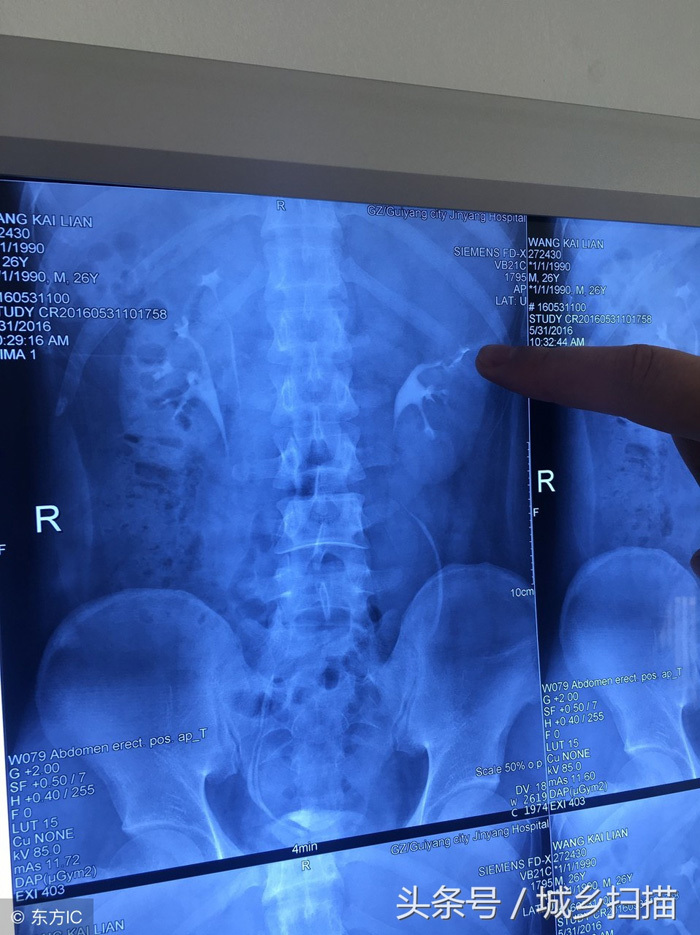

Vương Khai Luyện một lần bị đau dữ dội ở phần lưng eo, vì không chịu nổi mới đến bệnh viện kiểm tra. Sau khi kiểm tra, chụp X quang các bác sĩ phát hiện anh Vương có 4 quả thận. Bác sĩ cho biết, thận trên bên trái của anh bị ứ nước nghiêm trọng, bao phủ và chèn ép thận dưới bên trái, kèm theo nhiễm trùng gây ra một loạt các triệu chứng như đau lưng eo và sốt.

May mắn thay, sau nửa tháng điều trị, nhiễm trùng của anh Vương đã được kiểm soát. Bệnh viện đã nghiên cứu phương án phẫu thuật cắt bỏ và cuối cùng quyết định cắt bỏ thận trên bên trái bằng phẫu thuật nội soi xâm lấn tối thiểu, đây là phương pháp phẫu thuật tiên tiến nhất.

Ca phẫu thuật của Vương Khai Luyện khá thành công. Phẫu thuật nội soi chỉ lấy ra một vài lỗ nhỏ trên bụng bệnh nhân và cắt bỏ thành công quả thận trên bên trái của anh. Sau 10 ngày, Vương Khai Luyện được xuất viện.